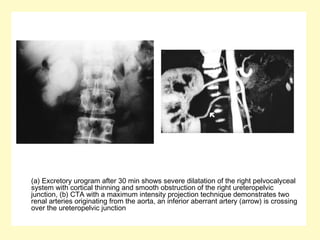

(a) Excretory urogram after 30 min shows severe dilatation of the right pelvocalyceal

system with cortical thinning and smooth obstruction of the right ureteropelvic

junction, (b) CTA with a maximum intensity projection technique demonstrates two

renal arteries originating from the aorta, an inferior aberrant artery (arrow) is crossing

over the ureteropelvic junction